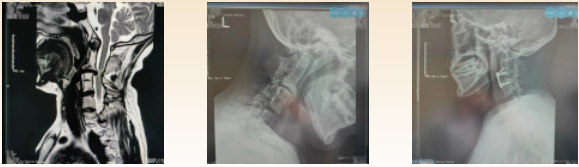

影检查提示:患者存在颈4/5椎间盘突出,相应节段脊髓受压变性,寰枕融合,颈2-4椎体及椎板、棘突融合,颈5-6椎体融合,颈5-6棘突隐裂,颈7椎体半椎畸形,颈7-胸1椎体融合,颈椎侧弯,左侧椎动脉发育缺如,椎枢关节失稳等一些列复杂的影像学表现。

经过术前详细的规划,反复的手术流程推演以及精细的术中操作,科室主任王直强带领团队顺利完成手术,切除的突出的椎间盘,使受压的颈脊髓得到充分减压,失稳的脊柱得到融合。麻醉苏醒后,患者即刻感觉左侧躯干、肢体麻木症状消失。